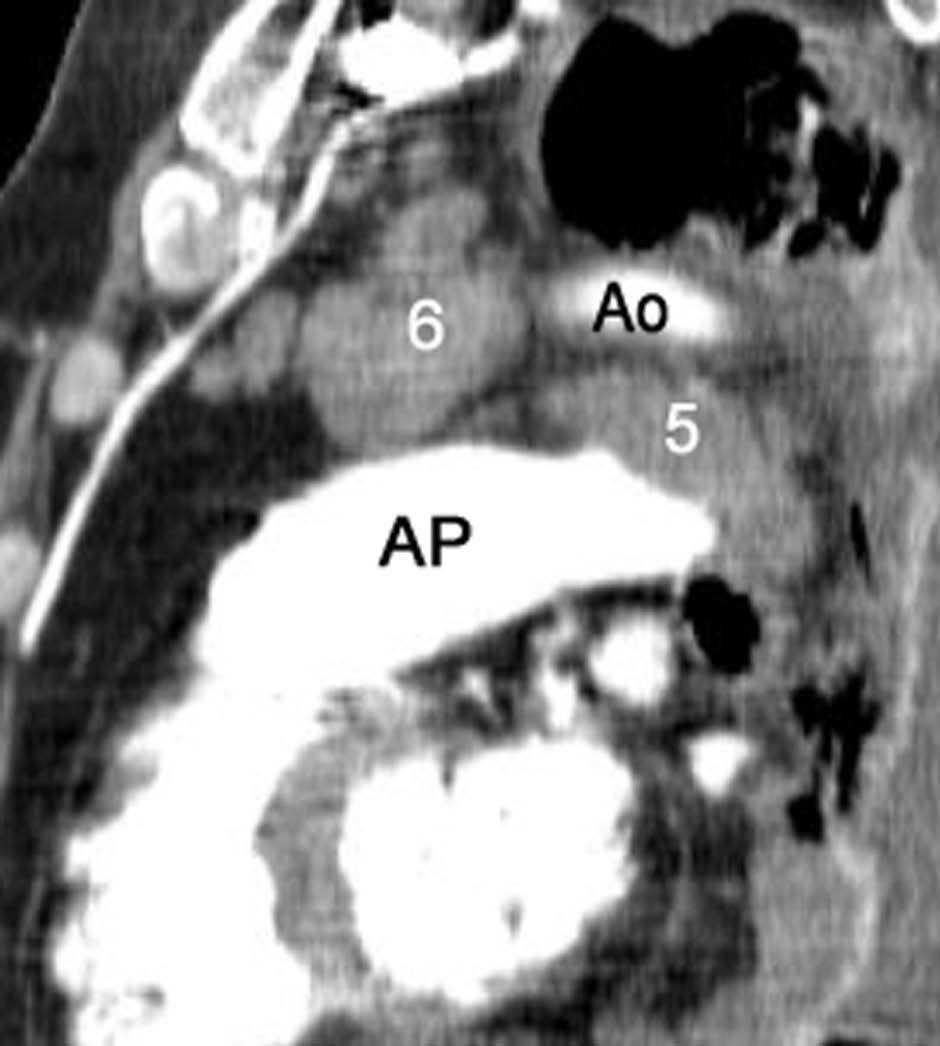

La precisión de la TC para predecir la afectación ganglionar mediastínica, pese a la ayuda que suponen las reconstrucciones MPR y 3D en la valoración de determinados territorios ganglionares (espacio subcarinal, hilio o ventana aortopulmonar) (fig. 11), sigue teniendo muchas limitaciones. El único criterio que se emplea para considerar que un ganglio es patológico es el tamaño (cuando el eje corto es mayor de 10 mm, salvo en el espacio subcarinal que se acepta hasta 12 mm). El empleo únicamente de criterios de tamaño hace que la TC sea una técnica poco precisa en la valoración de la afectación ganglionar. En un metaanálisis reciente13 la sensibilidad global de la TC para estadificar el mediastino fue de un 57%, con una especificidad del 82%, un valor predictivo positivo (VPP) del 56% y un valor predictivo negativo (VPN) del 83%. Lo que es innegable es la capacidad de la TC para mostrar un mapa de los ganglios tanto hiliares como mediastínicos (fig. 12), lo cual es de gran utilidad en la determinación del factor N. La valoración del territorio hiliar puede ser compleja por la agrupación de estructuras vasculares, por lo que además de la opacificación adecuada de éstas, es de utilidad la identificación de la pérdida del ángulo de la bifurcación (carina secundaria), ya que el eje corto significativo en este territorio es de 3 mm. Como ya hemos comentado, también es de gran ayuda en esta localización el empleo de reconstrucciones (fig. 11)5.

Fig. 12.--Estaciones ganglionares para la estadificación del cáncer de pulmón. Las reconstrucciones multiplanares (MPR) son de gran ayuda para precisar los territorios ganglionares afectos. Correlación de los territorios ganglionares entre el mapa ganglionar de Mountain y Dressler y una reconstrucción coronal de un paciente con afectación adenopática mediastínica e hiliar bilateral. (A y B) Ganglios mediastínicos superiores e inferiores e hiliares. (C y D) Ganglios aórticos. AP: arteria pulmonar. Ao: aorta.